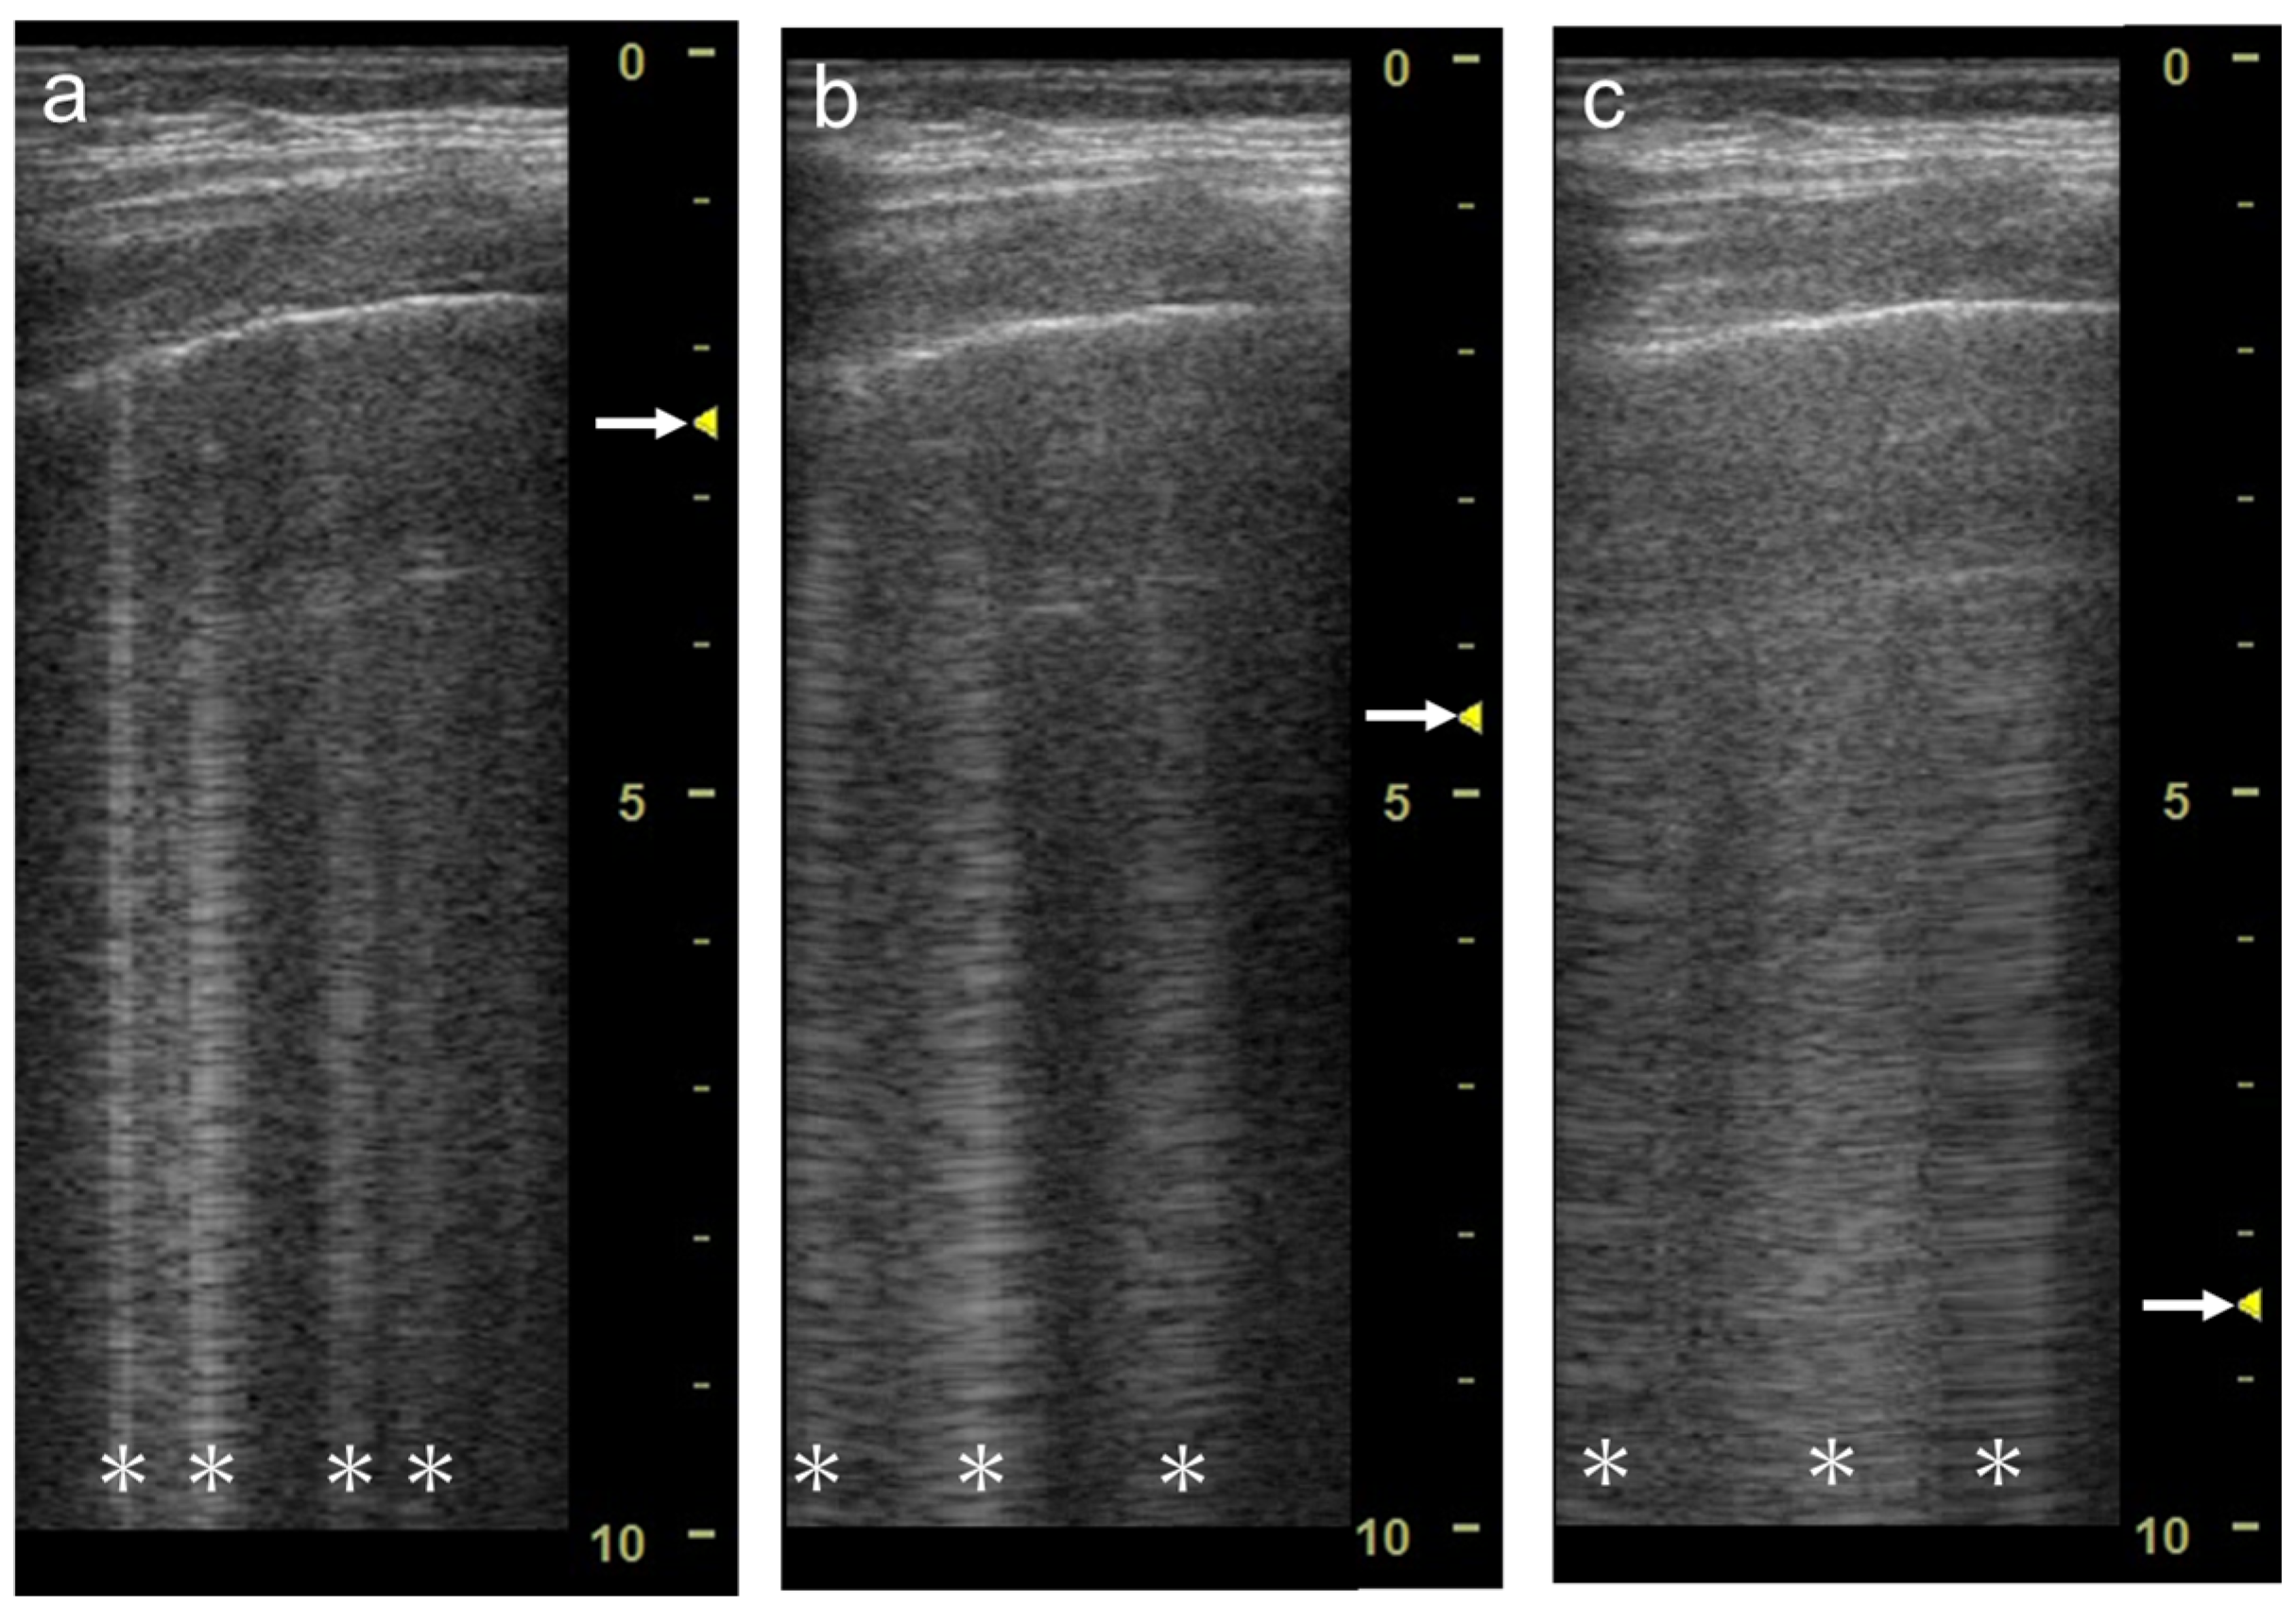

3.2. Focal Point

3.3. Frequency

3.4. Selection of Transducers